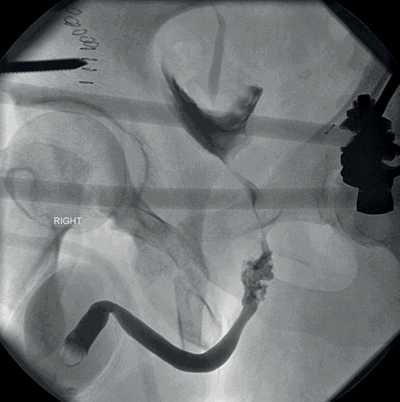

A 35-year-old male had a road traffic accident. He sustained a pelvic fracture with concomitant intra-abdominal visceral injuries, which were stabilised in the operating theatre.

He had blood at his urethral meatus.

1. Retrograde urethrogram.

2. Patient in 30° oblique position. If not possible, supine with AP views acceptable (may miss bulbar urethral extravasation). A 12F catheter is placed in the fossa navicularis and a seal formed with 2mls into the catheter balloon. 20-30mls of water soluble contrast injected slowly via the catheter. Fluoroscopic screening.

3. Partial (incomplete) posterior urethral injury (AAST Grade 3), with contrast passing into the bladder. Gentle attempt at urethral catheterisation can be attempted; if it fails a supra-pubic catheter can be inserted.

4.

Grade 1

Type of injury Contusion

Description of injury Blood at urethral meatus; retrography normal

Grade 2

Type of injury Stretch injury

Description of injury Elongation of urethra without extravasation on urethrography

Grade 3

Type of injury Partial disruption

Description of injury Extravasation of urethrography contrast at injury site with visualisation in the bladder

Grade 4

Type of injury Complete disruption

Description of injury Extravasation of urethrography contrast at injury site with visualisation in the bladder; <2cm of urethra separation

Grade 5

Description of injury Complete transection with ≥2cm urethral separation, or extension into the prostate or vagina